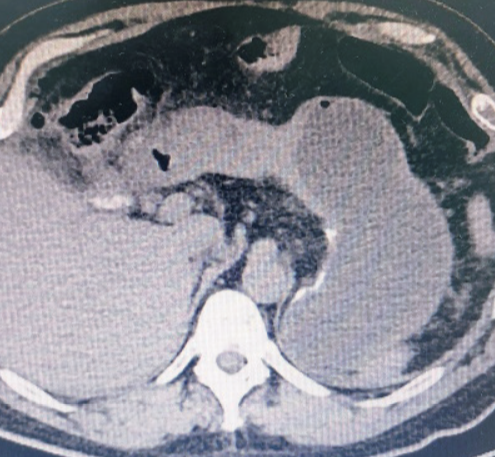

Varios factores de riesgo están implicados en el desarrollo del adenocarcinoma gástrico, como las cirugías gástricas previas1. En la cirugía de bypass gástrico se puede producir reflujo pancreaticobiliar crónico, con inflamación crónica en la mucosa gástrica. La aparición de adenocarcinoma gástrico del estómago excluido es rara y en esta condición específica tiende a diagnosticarse en estadios avanzados